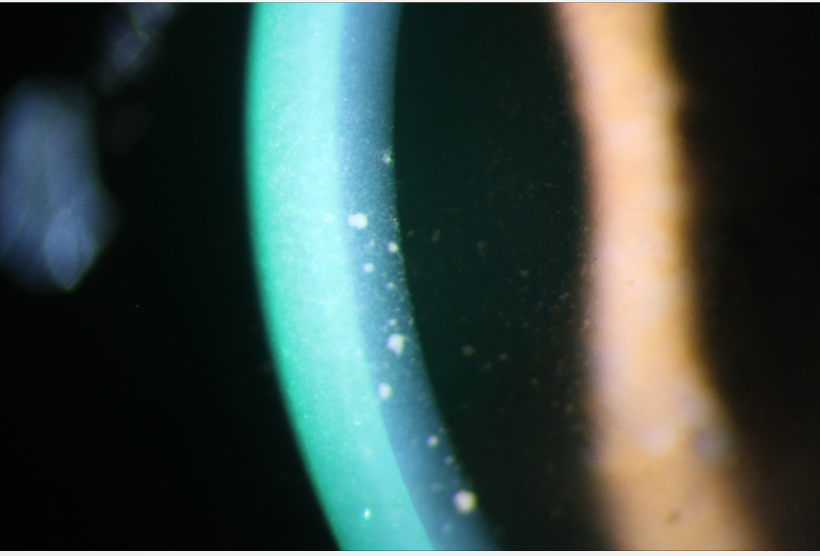

Below are pictures showing possible findings in some uveitis patients.

Keratic precipitates